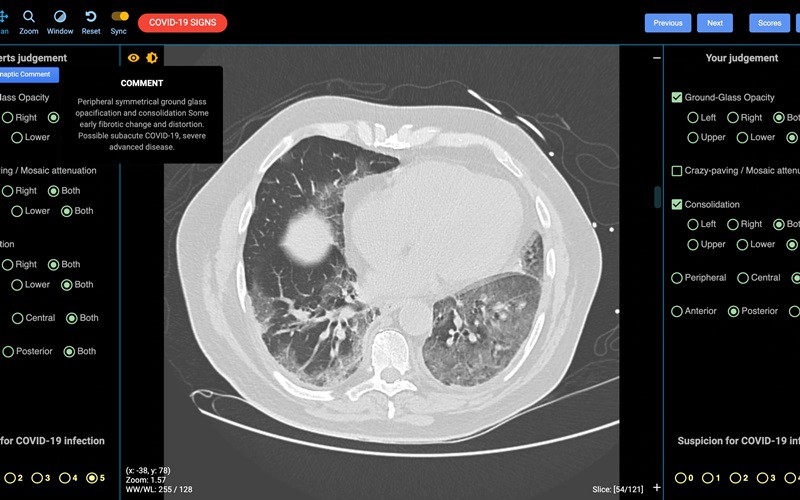

Ảnh chụp CT phổi người mắc Covid-19. Ảnh: Detected-X.

Trong một diễn biến khác có liên quan, ngày hôm nay (30/3), các nhà khoa học tại Đại học Sydney đã giới thiệu công cụ chẩn đoán Covid-19 đầu tiên trên thế giới có tác dụng giúp các bác sĩ nhanh chóng phân loại được bệnh nhân Covid-19. Công cụ có tên CovED mới này sẽ sử dụng hình chụp cắt lớp CT giúp các nhiên viên y tế tuyến đầu phát hiện các ca nhiễm Covid-19 chỉ trong vòng vài phút, nhanh hơn nhiều so với phương pháp xét nghiệm sinh hóa hiện nay.

Theo giáo sư Patrick Brennan, chuyên gia bức xạ y tế của Đại học Sydney, với công cụ chẩn đoán nhanh Covid-19 trên nền tảng trực tuyến này, các bác sĩ không được đào tạo chuyên sâu về chẩn đoán hình ảnh cũng có thể xác định được các bệnh nhân mắc Covid-19, giúp đẩy nhanh tốc độ phát hiện các ca nhiễm, hỗ trợhệ thống chăm sóc y tế đang quá tải và cứu sống được nhiều bệnh nhân./.